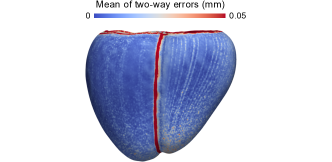

To assess the spatial distribution of transfer errors, we visualized their mean across all patients on the mean shape of the SSM. To avoid artifacts due to spatial interpolation, only errors directly available on the mean shape of the SSM were taken into account for this purpose, i.e., only one transfer direction was included.

The result in Fig. 17 (left) clearly shows that the two-way errors for UVC concentrate at discontinuities of the coordinates (compare with Fig. 1). Furthermore, there are large errors at the singularities of the rotational coordinate. For Cobiveco, these errors are greatly reduced, because only the transventricular coordinate is discontinuous and the origin of the apicobasal coordinate coincides exactly with the rotational singularities. Choosing narrower colormap limits to visualize the two-way errors for Cobiveco (Fig. S5) reveals the pattern of the isocurves used to compute the apicobasal coordinate (Fig. 13, bottom-left). These many non-zero, but still small errors explain the slight increase in the median two-way error observed for Cobiveco.

For the one-way error (Fig. 17, right), the discontinuities and singularities only play a minor role. It is dominated by inconsistencies of the coordinates across different geometries, which lead to inconsistent point correspondences. On average, the largest one-way errors occur at the RV outflow tract for Cobiveco and at the apical region of the LV lateral wall for UVC. Nevertheless, absolute errors are much smaller for Cobiveco.